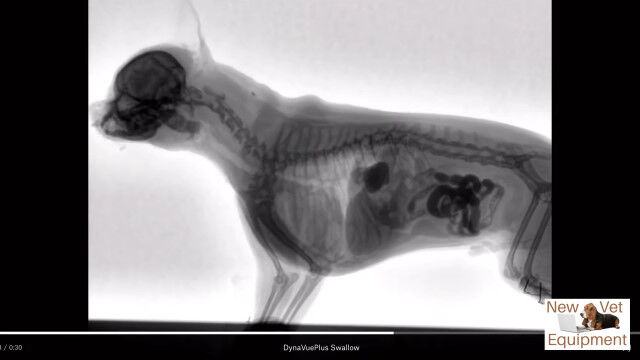

動物用レントゲンシステム、ダイナビューを用いて撮影された、犬がエサを食べる最中の体内の様子。

口から食道を通り、ゆっくり胃袋へ流れ込む様子が動画ではっきり確認できる。

Youtubeの概要欄に記載がなくて分からなかったけど、これ犬種はなんだろうね。

Veterinary Fluoroscopy - Watch the Swallow!